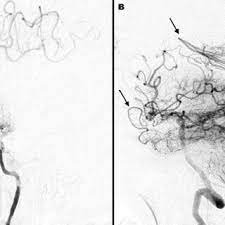

3. 신경영상검사(Neuroimaging): 뇌의 혈관 상태를 평가하기 위해 다양한 신경영상 검사가 사용됩니다. 주로 사용되는 검사에는 다음이 포함됩니다:

- 혈관조영술(Cerebral Angiography): 혈관조영술은 혈관 내부 구조를 자세하게 시각화하기 위해 사용됩니다. 이 절차는 모야모야병을 진단하는 가장 확실한 방법 중 하나입니다.

2. 혈관 조영술 (Cerebral Angioplasty): 혈관 조영술은 혈관 내부의 협착을 개선하기 위해 사용됩니다. 이 절차에서는 혈관 내부에 스텐트(Stent)를 배치할 수도 있습니다.

3. 혈관 이식 수술 (Bypass Surgery): 혈관 이식 수술은 모야모야병으로 인해 혈류가 차단된 부분을 우회하여 뇌 조직에 혈류를 공급하기 위해 사용됩니다. 이러한 수술은 중증의 모야모야병 환자에게 특히 효과적일 수 있습니다.